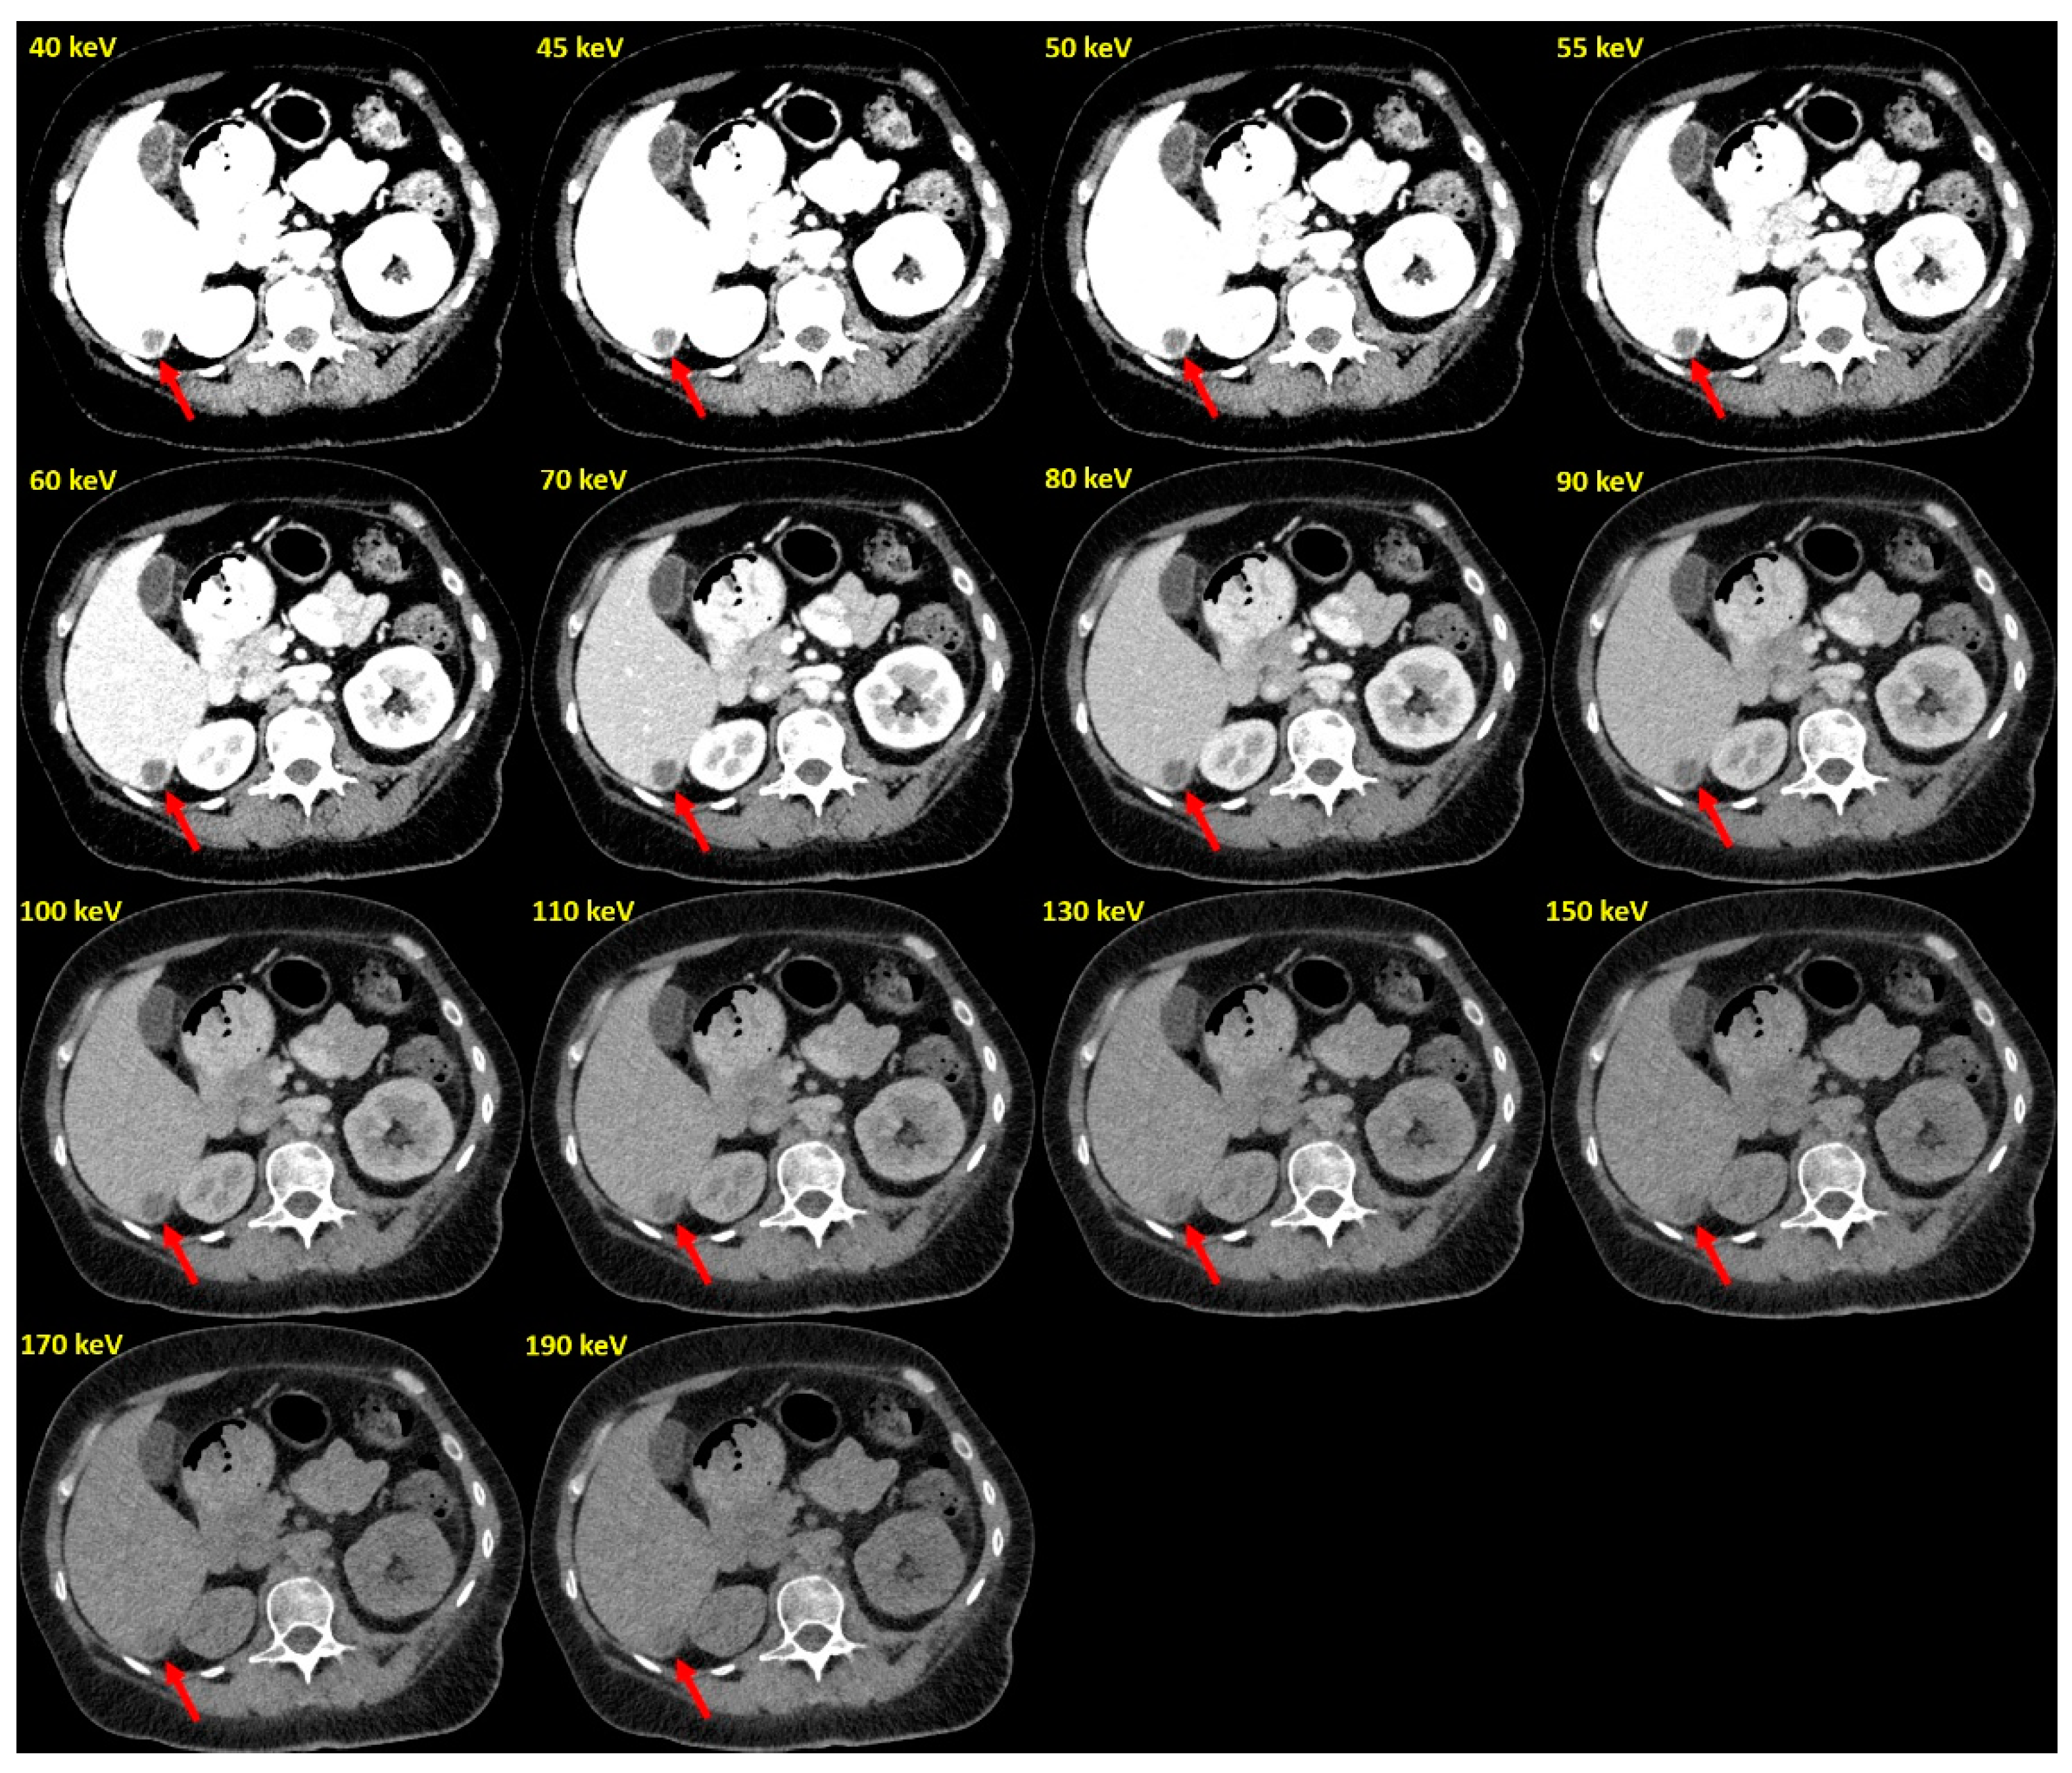

Optimal Conspicuity of Liver Metastases in Virtual Monochromatic Imaging Reconstructions on a Novel Photon-Counting Detector CT—Effect of keV Settings and BMI

2. Materials and Methods

2.1. Scan Protocol and Reconstruction Settings

2.2. Image Postprocessing and Analysis